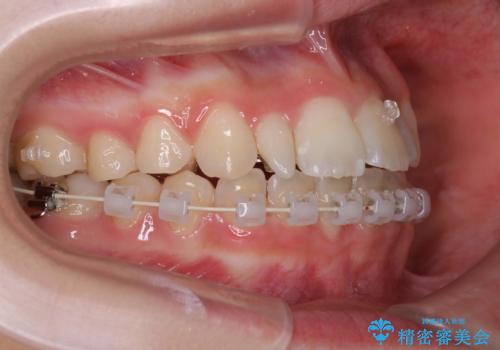

- 矯正装置

- ハーフリンガル

- ハーフリンガルシステムによる矯正治療を行いながら、スペースコントロールをみて前歯を仮歯へ

→矯正の終了をメドに仮歯をセラミックへ置き換える

このような場合、矯正によりスペースを集め、本来あるべき形態にセラミックで修正することもできます。